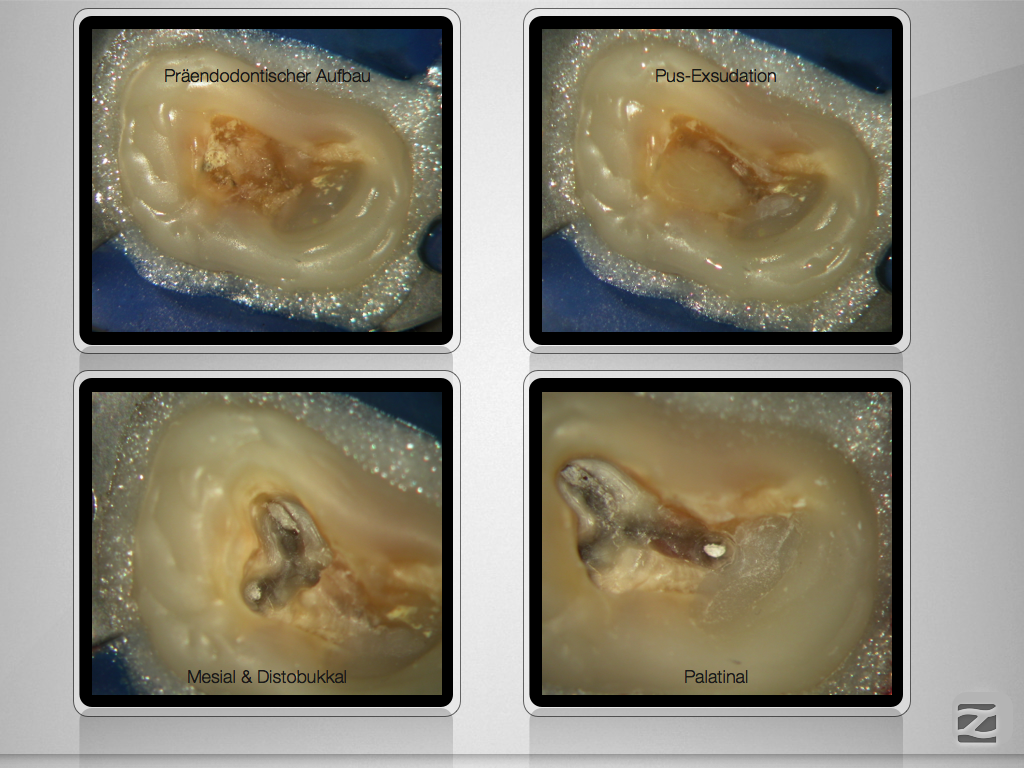

Hyflex Fallbeispiel (3/3)